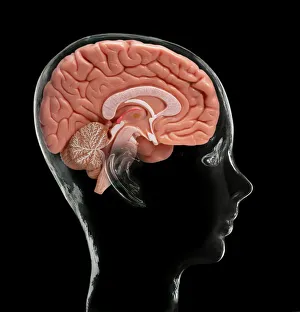

The central nervous system, the intricate network that governs our every thought and movement, is a marvel of complexity. From the delicate cerebellum tissue to the detailed light micrograph capturing its essence, we are reminded of its importance in maintaining balance and coordination. Anatomy comes alive as we explore the human brain from an inferior view. The intricacy of brain fibers is revealed through DTI MRI scans like C017/7099 and C017/7035, showcasing their vital role in transmitting information throughout this extraordinary organ. Artistic renderings bring us closer to understanding the medulla oblongata's significance within the brain. Its portrayal in various artworks allows us to appreciate how it controls essential functions such as breathing and heart rate. As we delve deeper into studying the central nervous system, models of the human brain provide invaluable insights into its structure and organization. Lateral views reveal countless regions responsible for cognition, emotion regulation, sensory perception, and motor control. Microscope slides offer glimpses into nerve cells' intricate architecture—a testament to their ability to transmit electrical signals at lightning speed. Meanwhile, glial stem cell cultures captured under a light microscope remind us of their crucial role in supporting neuronal function. Finally, artistic representations unveil the limbic system's enigmatic nature—an interconnected web responsible for emotions and memory formation. These captivating artworks allow us to visualize this complex network within our brains. Exploring these hints provides a glimpse into the awe-inspiring world of our central nervous system—the very foundation upon which our thoughts, actions, memories reside—reminding us just how remarkable our brains truly are.